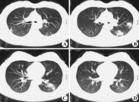

1.肺內大片狀緻密陰影,邊續模糊,繼而出現厚壁空洞,內壁光整或不規則,可見液平。

2.形成張力性空洞,壁薄,可壓迫周圍肺組織或縱隔。

3.可伴有少量胸腔積液、膿胸或膿氣胸。

4.體層攝影、CT、MR有助於病灶形態內部結構和與周圍組織器官的三維立體觀察。